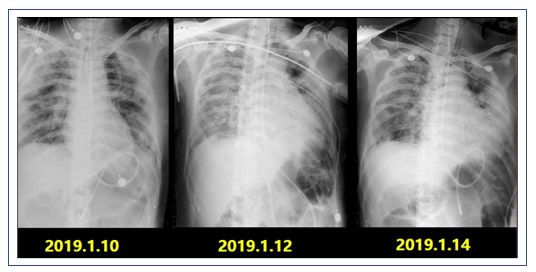

2019年1月10日,再次高热39.1℃,无伴明显畏寒、寒战;间伴有烦躁发作。患者1月10日后反复发热,氧合变差,多次肺部影像学提示;双肺多发渗出灶较前进展。Cstat(呼吸系统静态顺应性)22-30,肺顺应性差。

复查X线胸片:双肺多发渗出进展,左肺大片实变(图6)。

2019年1月16日复查胸部CT:双侧中下肺实变影较1月9日增多(图7)。